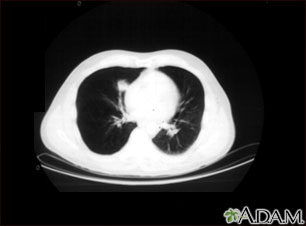

A CT scan showing a mass in right lower chest near the heart (left side of photograph).